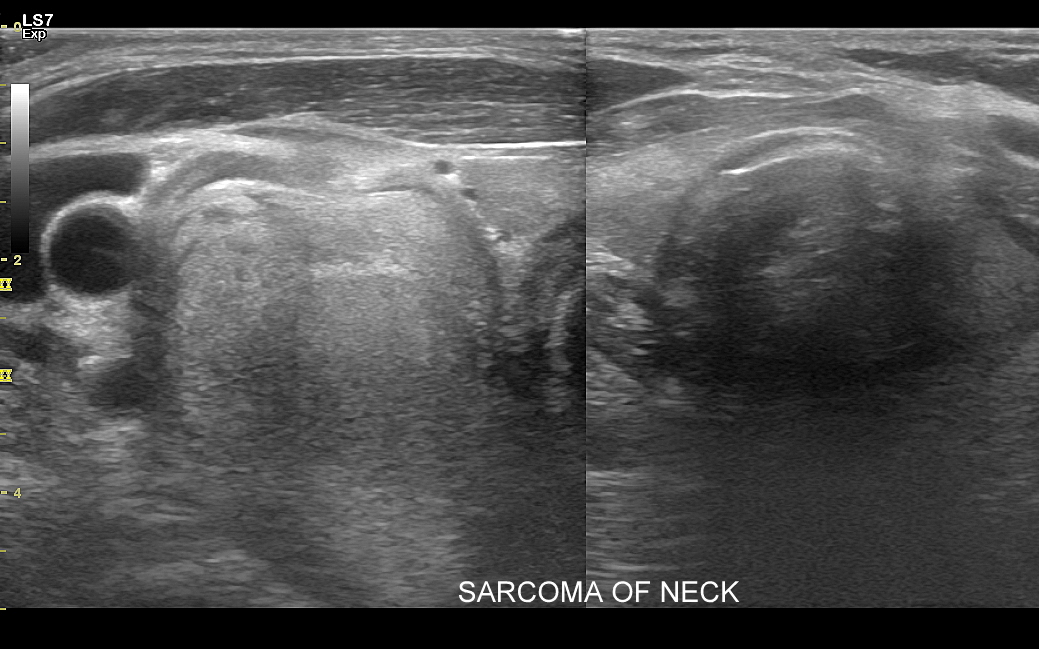

Badanie USG jest podstawową metodą obrazowania węzłów chłonnych. W jego trakcie ocenia się nie tylko wielkość węzłów, lecz także ich kształt, proporcje wymiarów, morfologię, czyli wygląd zewnętrzny oraz strukturę wewnętrzną, ich unaczynienie, spoistość, a także tkanki otoczające. W trakcie interpretacji badania pod uwagę bierze się również zbierany od pacjenta wywiad chorobowy oraz wyniki innych badań obrazowych i laboratoryjnych takich jak morfologia, OB, CRP, żelazo, ferrytyna, TIBC, innych parametrów infekcyjnych, a także onkologicznych. Ultrasonografia węzłów chłonnych jest procedurą bezpieczną i dokładną. W Pracowni dr Szczepańskiego węzły chłonne oceniane są nowoczesną metodą MPUS (multiparametryczne badanie USG), w szczególności z zastosowaniem trybów mikrounaczynienia i elastografii.

Do powiększenia węzłów chłonnych szyi, stanu określanego jako limfadenopatia, dochodzi najczęściej w przebiegu chorób zakaźnych górnych dróg oddechowych, wirusowych i bakteryjnych. Inne przykłady przyczyn limfadenopatii szyjnej obejmują ropne choroby zębów, migdałków i zatok przynosowych; odczyny w chorobach autoimmunologicznych, np. w chorobie Hashimoto i Sjögrena; a także rozrostowe schorzenia układu hematologicznego (białaczki i chłoniaki) i choroby nowotworowe jak np. rak tarczycy, krtani, migdałka, czy języka. Należy mieć na uwadze, iż w przypadku podejrzenia chorób układu krwiotwórczego oraz mononukleozy zakaźnej, oprócz węzłów chłonnych, niezbędne jest również badanie USG wątroby i śledziony. W części przypadków, gdy podejrzewa się możliwość choroby nowotworowej lub w celu jej wykluczenia, lekarz może zalecić rozszerzenie diagnostyki obrazowej na inne obszary ciała.